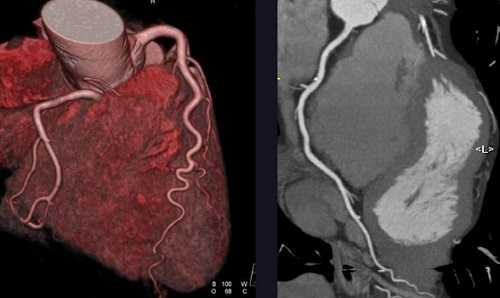

КТ ангиография что показывает

КТ-ангиография кровеносной сети головного мозга

Компьютерная томографическая ангиография (КТА) имеет ряд особенностей. Для исследования сосудистого русла используют специальный сканер, который позволяет получить детальное изображение при постоянной пульсации вен и артерий.

Мультиспиральная КТ ангиография, трехмерная визуализация

КТ ангиография позволяет создать трехмерную реконструкцию сосудистой системы на определенном участке. В отличие от классической рентгенографии в результате исследования получают серию послойных изображений с заданным шагом. Толщину сканирующего среза настраивают индивидуально (от 1 мм). На основании поперечных, боковых и прямых фото создают 3D-модель рассматриваемой области.

КТА отражает особенности строения вен и артерий головного мозга, легких, внутренних органов, периферических сосудов верхних и нижних конечностей. При проведении КТ ангиографии изучают состояние аорты, оценивают характер коронарного кровоснабжения.

На основании ангиографии с применением компьютерной томографии диагностируют:

- атеросклероз;

- диссекцию (расслоение) аорты;

- аневризмы, в том числе малого размера;

- артерио-венозные мальформации;

- стенозы, окклюзии;

- тромбозы;

- эмболии;

- васкулиты;

- ишемическую болезнь сердца;

- сосудистые новообразования добро- и злокачественного характера;

- травматические поражения сосудов и последствия кровотечений;

- геморрагические и ишемические инсульты.

Томограммы показывают состояние сосудистой стенки, визуализируют утолщение, расслоение при воспалительных процессах и нарушение целостности при различных повреждениях.